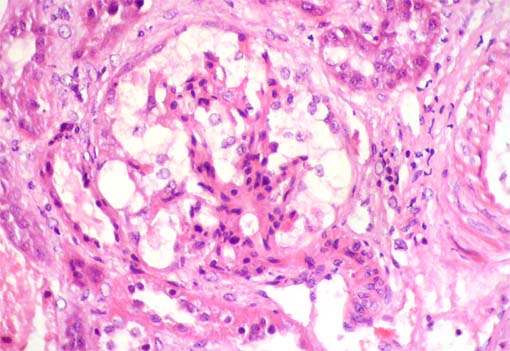

See the images of the renal biopsy.

Figure 1.

H&E, X200.

Figure 2.

H&E, X400.